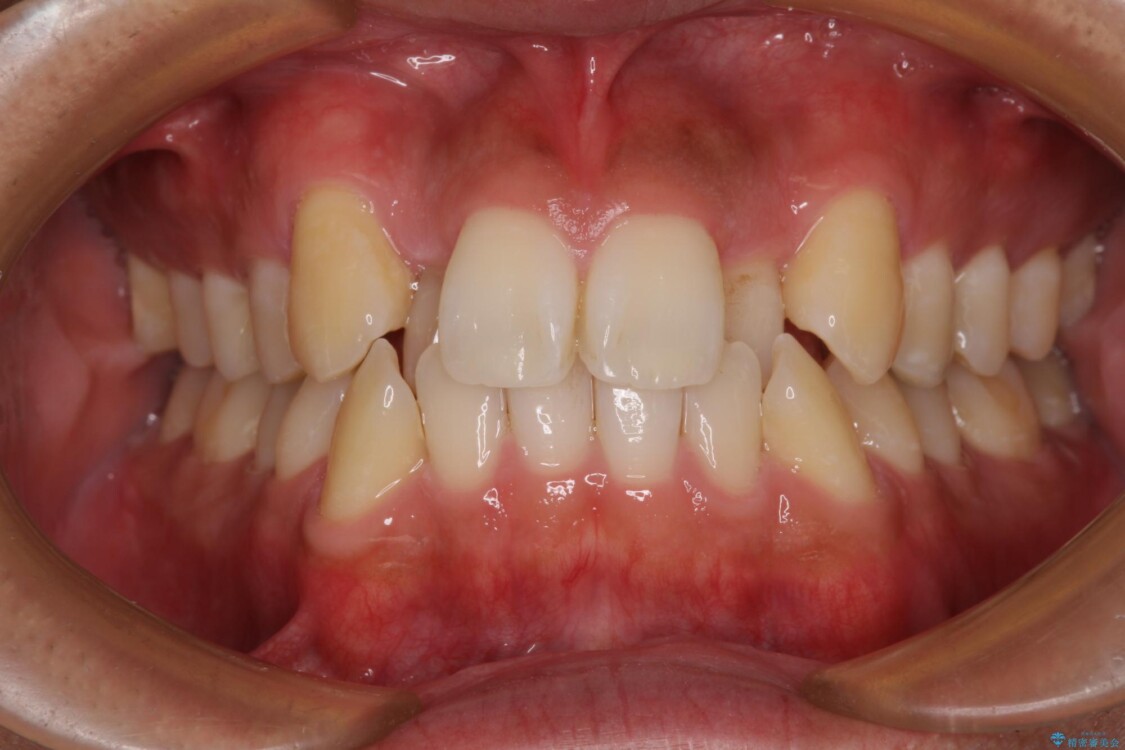

治療後

八重歯はきれいに整い、前歯もバランスよく収まり、横顔のラインも自然に改善されました。

治療後、患者様は「思い切り笑えるようになった」と大変喜んでくださいました。